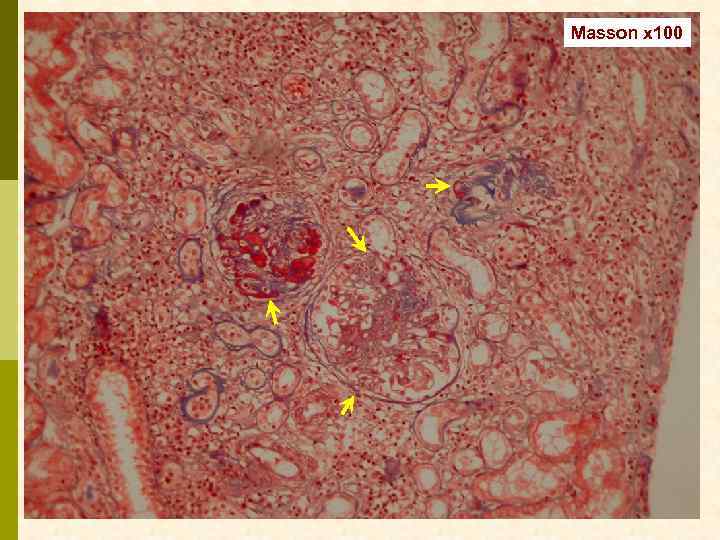

Б. Клинический случай № 21631 Александр К. , 1972 г. рожд. В 1999 г. выявлен гепатит С, в 2003 г. – ВИЧ. С июня 2006 г. – отеки, быстрое развитие анасарки. Почки по УЗИ 13 7 см. Протеинурия 9, 6 г/сут, креатинин 0, 19 мм/л, холестерин 18 мм/л. Обнаружен Ig. M-криоглобулин. 02. 11. 2006 - диагностическая нефробиопсия.

PAS x 100

Masson x 100

Masson x 100

Jones x 100

Jones x 100

PAS x 400

PAS x 400

Jones x 400

Jones x 400

Masson x 400

Masson x 400

Masson x 400

Иммунофлюоресцентное исследование: p Клубочки: Ig. G (2+), Ig. M (3+), C 3 (2+), kappa (3+), lambda (1 -2+) - диффузная, субэндотелиальная и интракапиллярная, крупно-гранулярная экспрессия; p Стенки артериол: C 3 (2+); p Цилиндры: Ig. G (2+), Ig. A (3+), Ig. M (2+), C 3 (3+), kappa (3+), lambda (2+); p Реабсорбированные белковые капли: kappa (3+).

Предварительное гистологическое заключение: p Мембрано-пролиферативный, HCV-ассоциированный, криоглобулинемический(? ) гломерулонефрит с полным склерозом 47% клубочков, сегментарным склерозом 22% клубочков и формированием полулуний в 15% клубочков; p диффузно-очаговый выраженный острый канальцевый некроз; p выраженный артерио-артериолосклероз. Примечание: Криоглобулинемическая природа поражения будет уточняться при ЭМ-исследовании.

Заключение p Мембрано-пролиферативный гломерулонефрит, криоглобулинемический, ВИЧ-ассоциированный, на фоне гепатита С